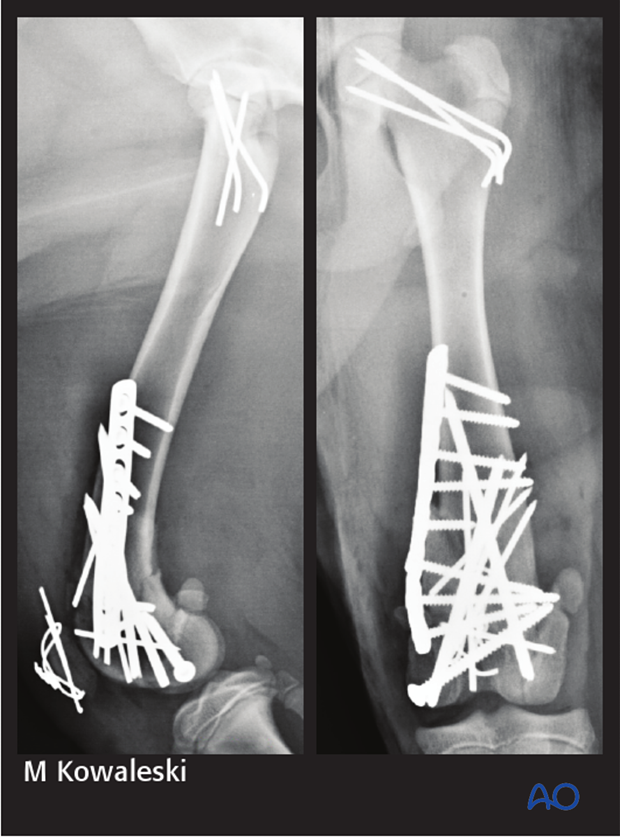

Post-operative radiographs demonstrate good alignment after fracture repair using a combination of screws, pins, and a bridging plate. The patellar fracture was repaired with a pin and tension band technique. The 31-B2 fracture was repaired with smooth pins.